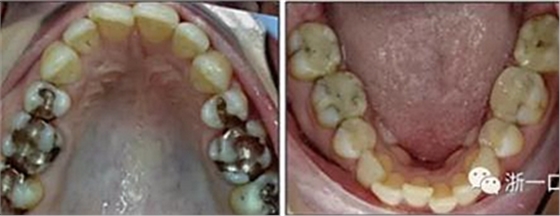

患者曾行正畸治療,現(xiàn)覺(jué)笑容不美觀前來(lái)就診?;颊哒嬗^及側(cè)貌示下頜發(fā)育不足,偏高角,唇閉合不全。上下頜中線(xiàn)齊。覆合、覆蓋4毫米。磨牙關(guān)系及尖牙關(guān)系II類(lèi)。上頜擁擠度4mm,下頜擁擠度6mm。4顆第一前磨牙在第一次正畸治療時(shí)已拔除。上下牙弓呈尖圓型,牙弓狹窄。

由于下頜中切牙間沒(méi)有間隙行下頜正中切開(kāi)術(shù),故進(jìn)行術(shù)前正畸擴(kuò)展間隙。下頜前牙粘托槽,中切牙托槽成交放置,將中切牙牙根分開(kāi)。使用0.018X0.018鎳鈦絲及置于下頜左、右中切牙之間的推簧推間隙。3個(gè)月后拍攝CBCT示已有足夠間隙行下頜正中截骨術(shù)。